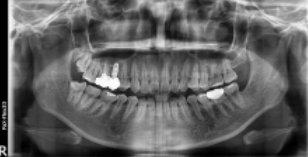

왼쪽 사진에 보시면 빨간색 네모 박스 보이시나요? 이 부분의 치아가 상실되어 임플란트가 필요한 상황이었습니다.

바로 옆에 있는 골드크라운 치아도 교체가 필요한 상황이라.. 임플란트와 골드크라운 교체를 함께 진행하기로 결정하셨는데요.

우측 엑스레이 보시면, 치아 뿌리가 남아있는 상황으로 '치아 뿌리 발치'가 먼저 필요한 상황이었습니다. 방치하게 되면, 통증이 더 심해질 수 있기에 빠르게 발치를 먼저 진행하셨습니다.